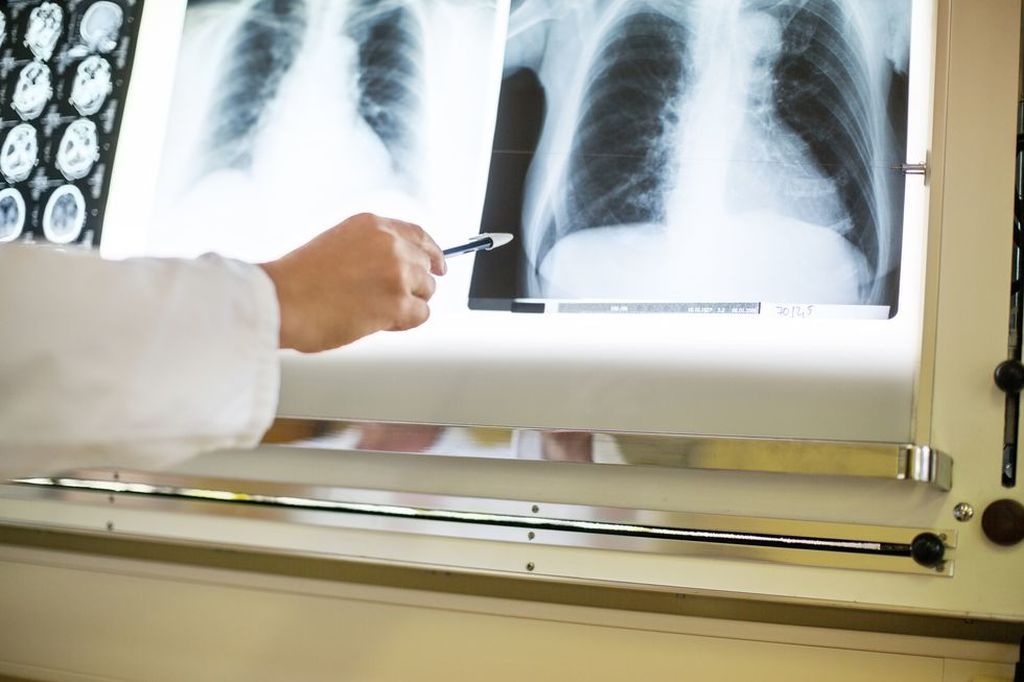

Saiba Como Interpretar Radiografia Blog Ipemed

Desvendando O Raio X De Torax Sanar Medicina

www.sanarmed.com